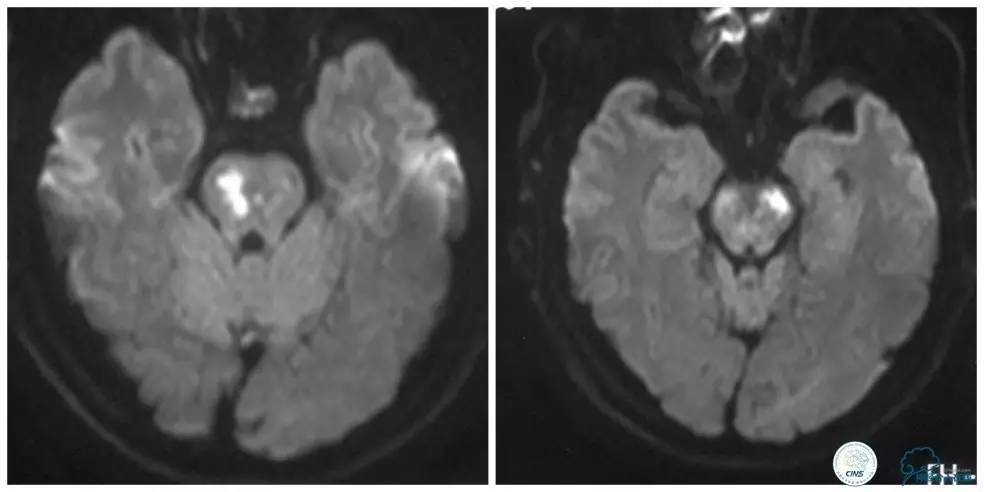

外院头颅MR:脑桥梗死(图1)。

图1